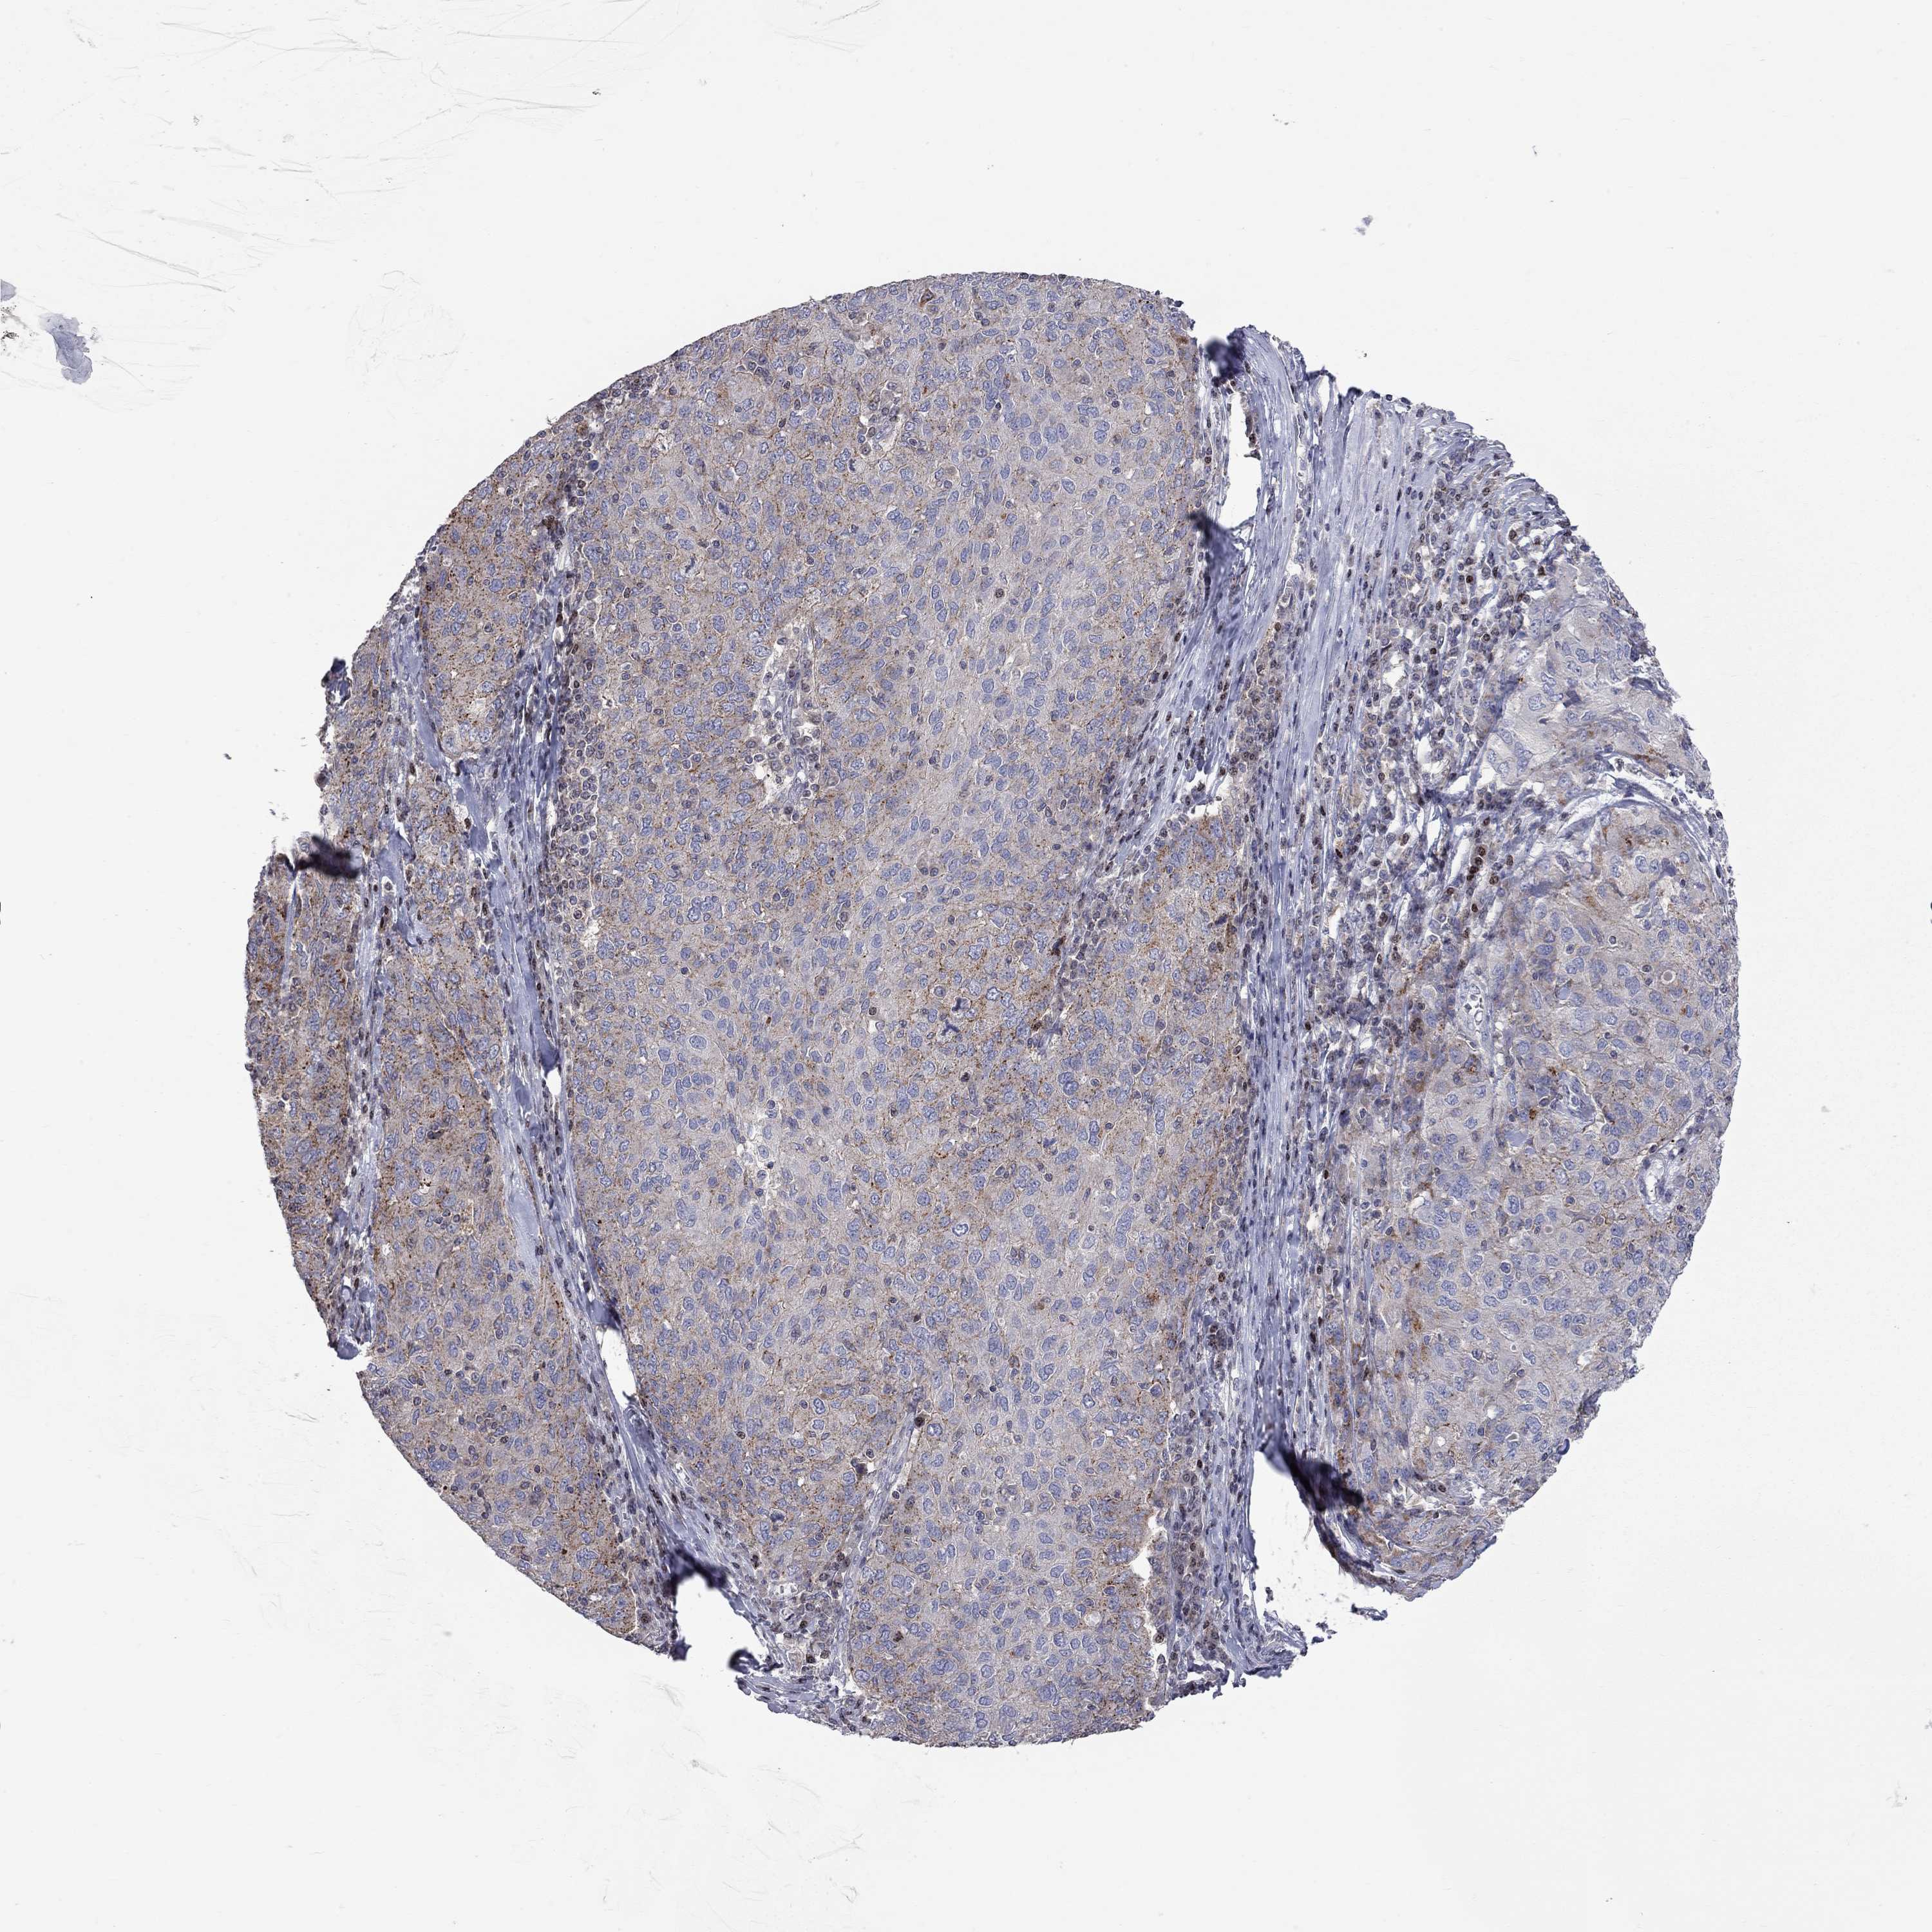

OVARIAN CANCER - Protein expressioni

A mouse-over function shows sample information and annotation data. Click on an image to view it in a full screen mode. Samples can be filtered based on level of antibody staining by selecting one or several of the following categories: high, medium, low and not detected. The assay and annotation is described here.

Note that samples used for immunohistochemistry by the Human Protein Atlas do not correspond to samples in the TCGA dataset.

Antibody stainingi

Antibody staining in the annotated cell types in the current human tissue is reported as not detected, low, medium, or high, based on conventional immunohistochemistry profiling in selected tissues. This score is based on the combination of the staining intensity and fraction of stained cells.

Each image is clickable and will lead to virtual microscopy that enables deeper exploration of all samples and also displays staining intensity scores, fraction scores and subcellular localization as well as patient and tissue information for each sample.

Antibody HPA076875

Staining

High

Medium

Low

Not detected

Intensity

Strong

Moderate

Weak

Negative

Quantity

>75%

75%-25%

<25%

None

Location

Nuclear

Cytoplasmic/membranous

Cytoplasmic/membranous,nuclear

Cystadenocarcinoma, serous, NOS

Cystadenocarcinoma, mucinous, NOS

Carcinoma, endometroid